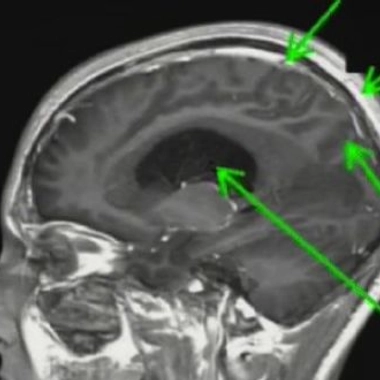

Hydrocéphalie, une tête qui grossit